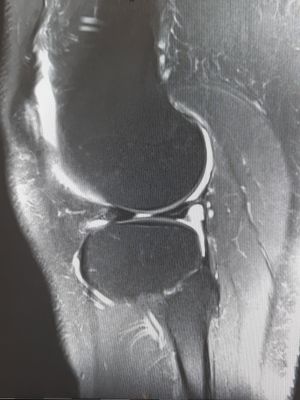

Klinik und Diagnose

Es entstehen Schmerzen im Kniebereich mit teils eingeschränkter Beweglichkeit. Die klinische Untersuchung kann bereits mit hoher Wahrscheinlichkeit einen Hinweis für einen Meniskusriss geben. Eine MRT-Untersuchung ist aber erforderlich, um die Verdachtsdiagnose zu bestätigen und Begleitpathologien zu erkennen.

Die Anamneseerhebung sowie eine entsprechende klinische Untersuchung lassen bereits auf eine Kreuzbandruptur schließen. Es werden Röntgenaufnahmen in zwei Ebenen zum Ausschluss knöcherner Verletzungen durchgeführt. Die Bildgebung der Wahl ist aber eine MRT- Untersuchung, um die Diagnose abzusichern und um Begleitverletzungen zu erkennen.

Ein Röntgen und im Anschluss eine MRT-Abklärung mit Knorpelsequenzen sind zur Diagnosesicherung erforderlich.